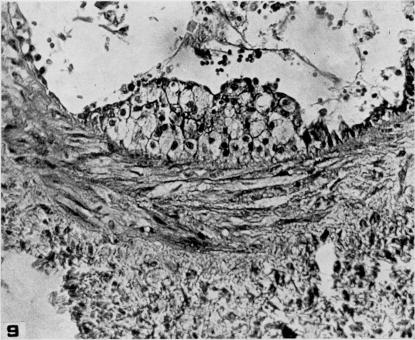

Studies on the pathogenesis of vascular disease; the effect of intravenous egg-yolk emulsions on inflammatory lesions of the aorta and coronary arteries of dogs.

Yale J Biol Med. 1956 Sep;29(1):9-22.